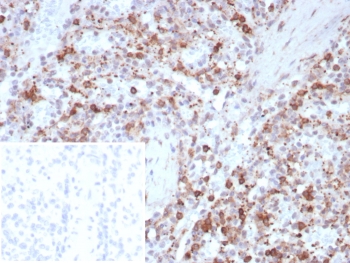

Immunohistochemistry analysis of Osteonectin antibody in human spleen tissue (clone rOSTN/8527). FFPE human spleen sections demonstrate HRP-DAB brown cytoplasmic and extracellular staining in stromal cells and matrix-rich areas within the splenic parenchyma. Numerous scattered positive cells are observed, consistent with Secreted protein acidic and rich in cysteine expression in the extracellular matrix and supporting stromal compartment. The inset shows PBS used in place of primary antibody, serving as a secondary antibody negative control with absence of specific brown staining. Heat induced epitope retrieval was performed by boiling tissue sections in pH 9 10 mM Tris with 1 mM EDTA for 20 minutes followed by cooling prior to antibody incubation.